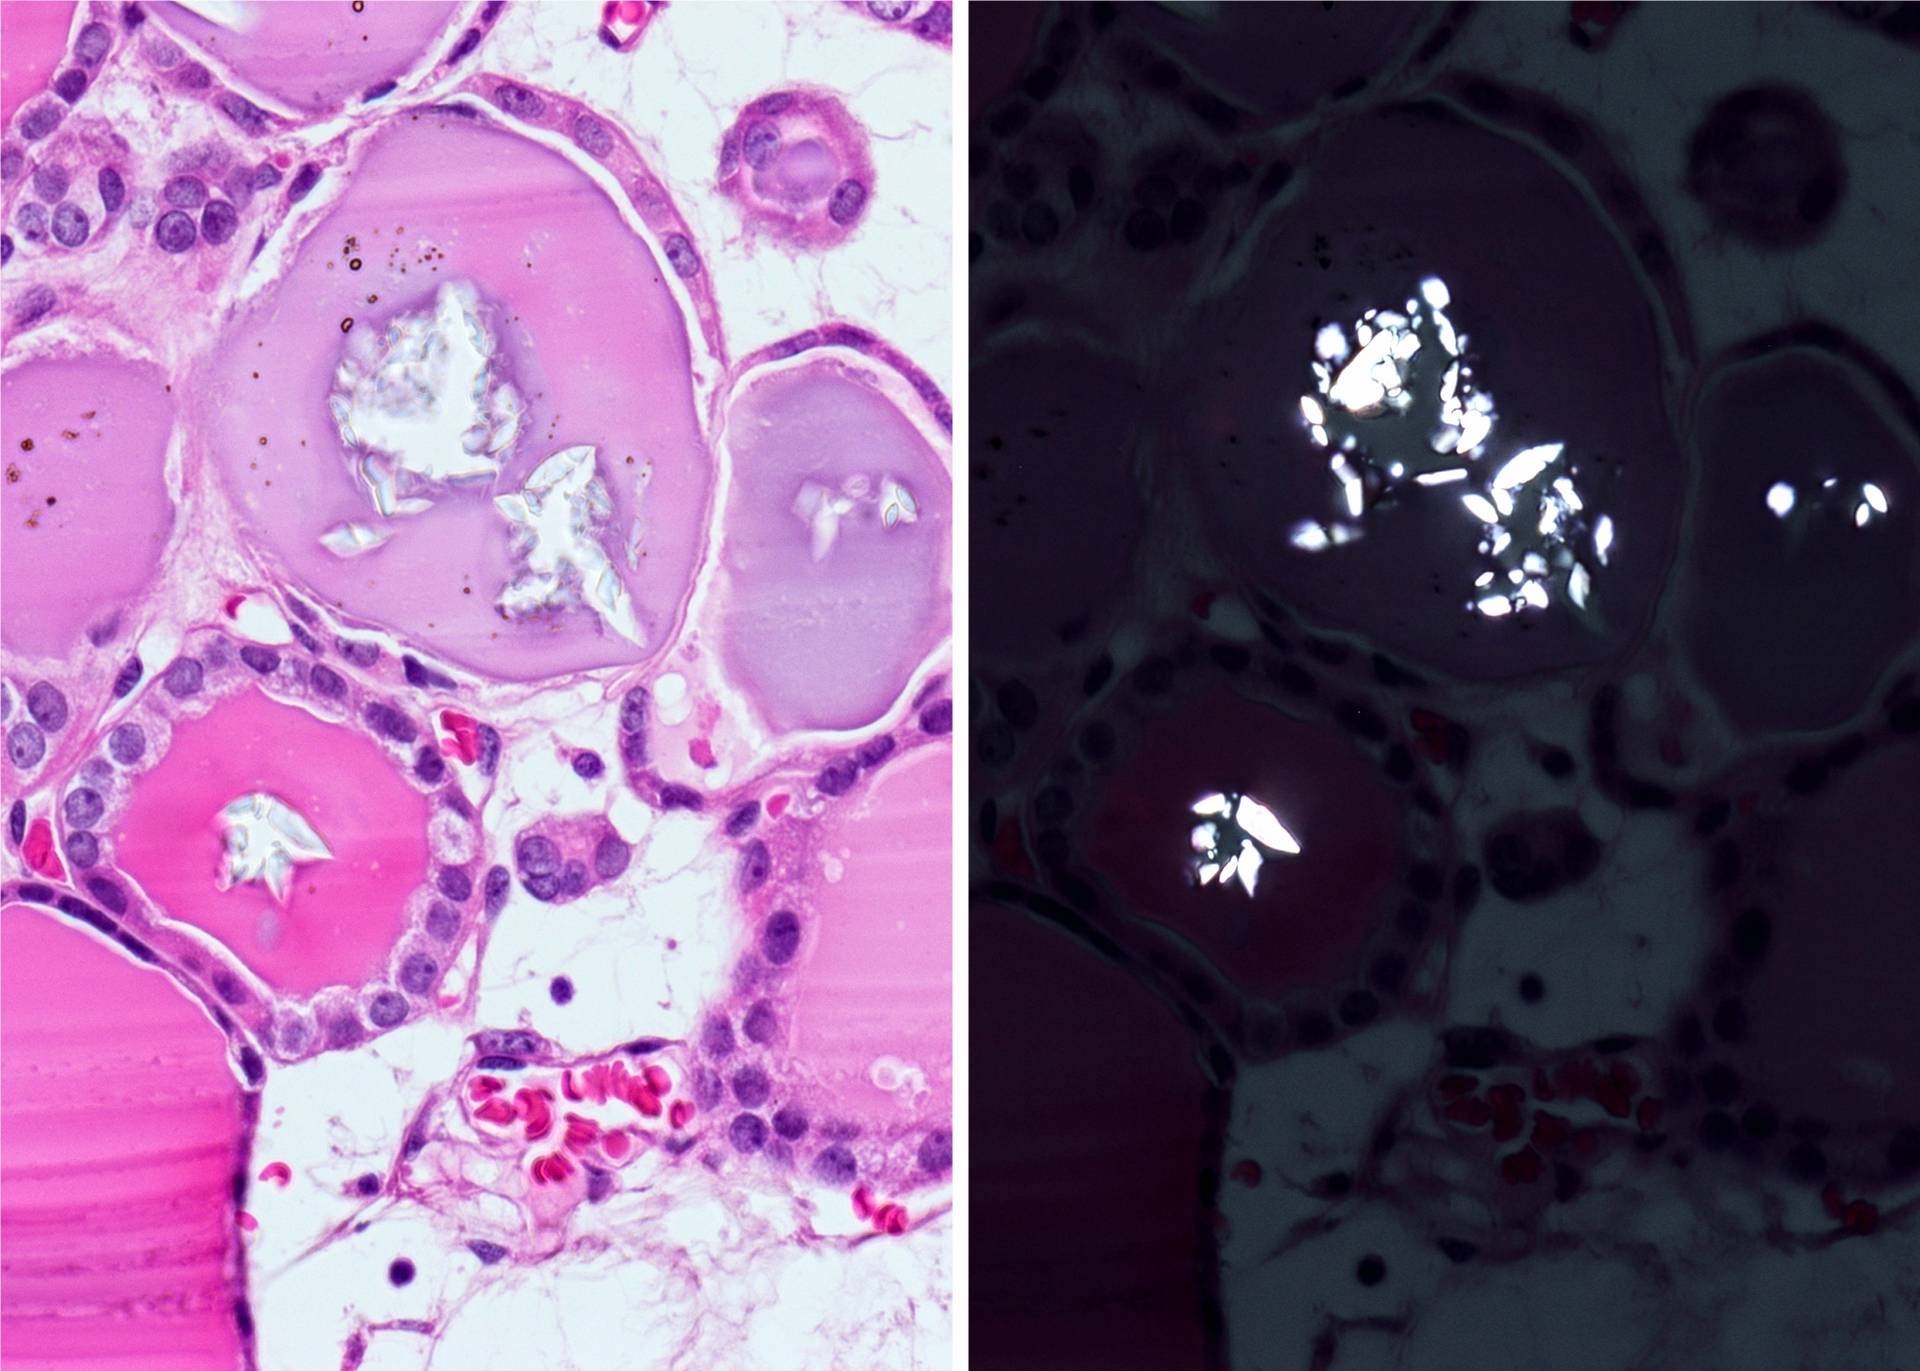

- Macrofollicular (colloid): large follicles, flattened epithelium, abundant colloid

- Secondary changes: fibrosis, hyalinization, hemorrhage, hemosiderin deposition, edema, cystic degeneration, calcification, osseous or cartilaginous metaplasia

Microscopic (histologic) images

Contributed by Shipra Agarwal, M.D., Andrey Bychkov, M.D., Ph.D., Mark R. Wick, M.D., Asmaa Gaber Abdou, M.D. and AFIP

Patterns:

Atypical adenomas:

Not invasion: